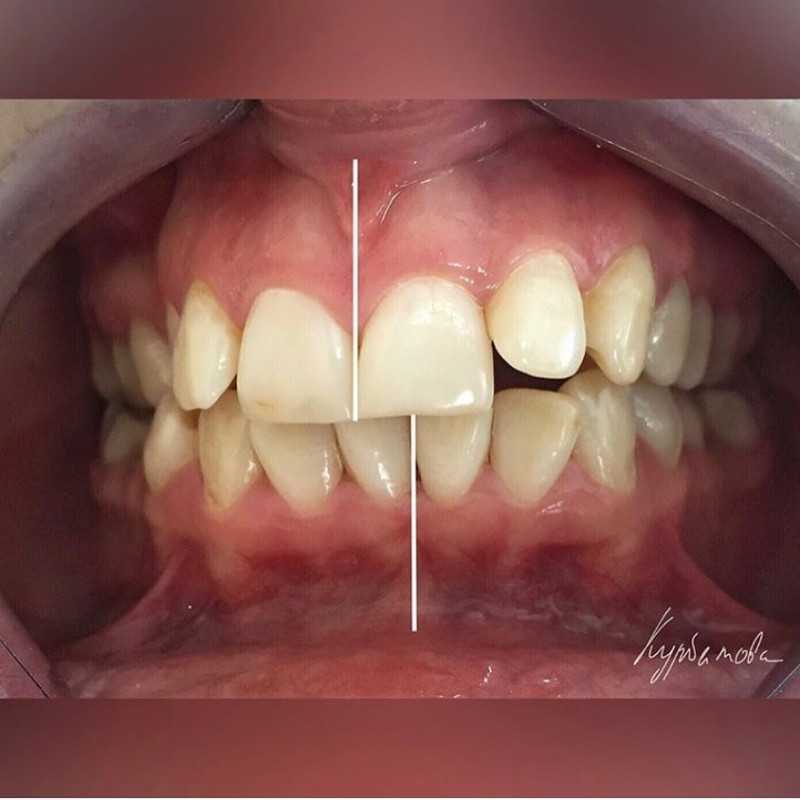

Установка самолигирующих брекетов

Доктор: Курбатова Юлия Викторовна